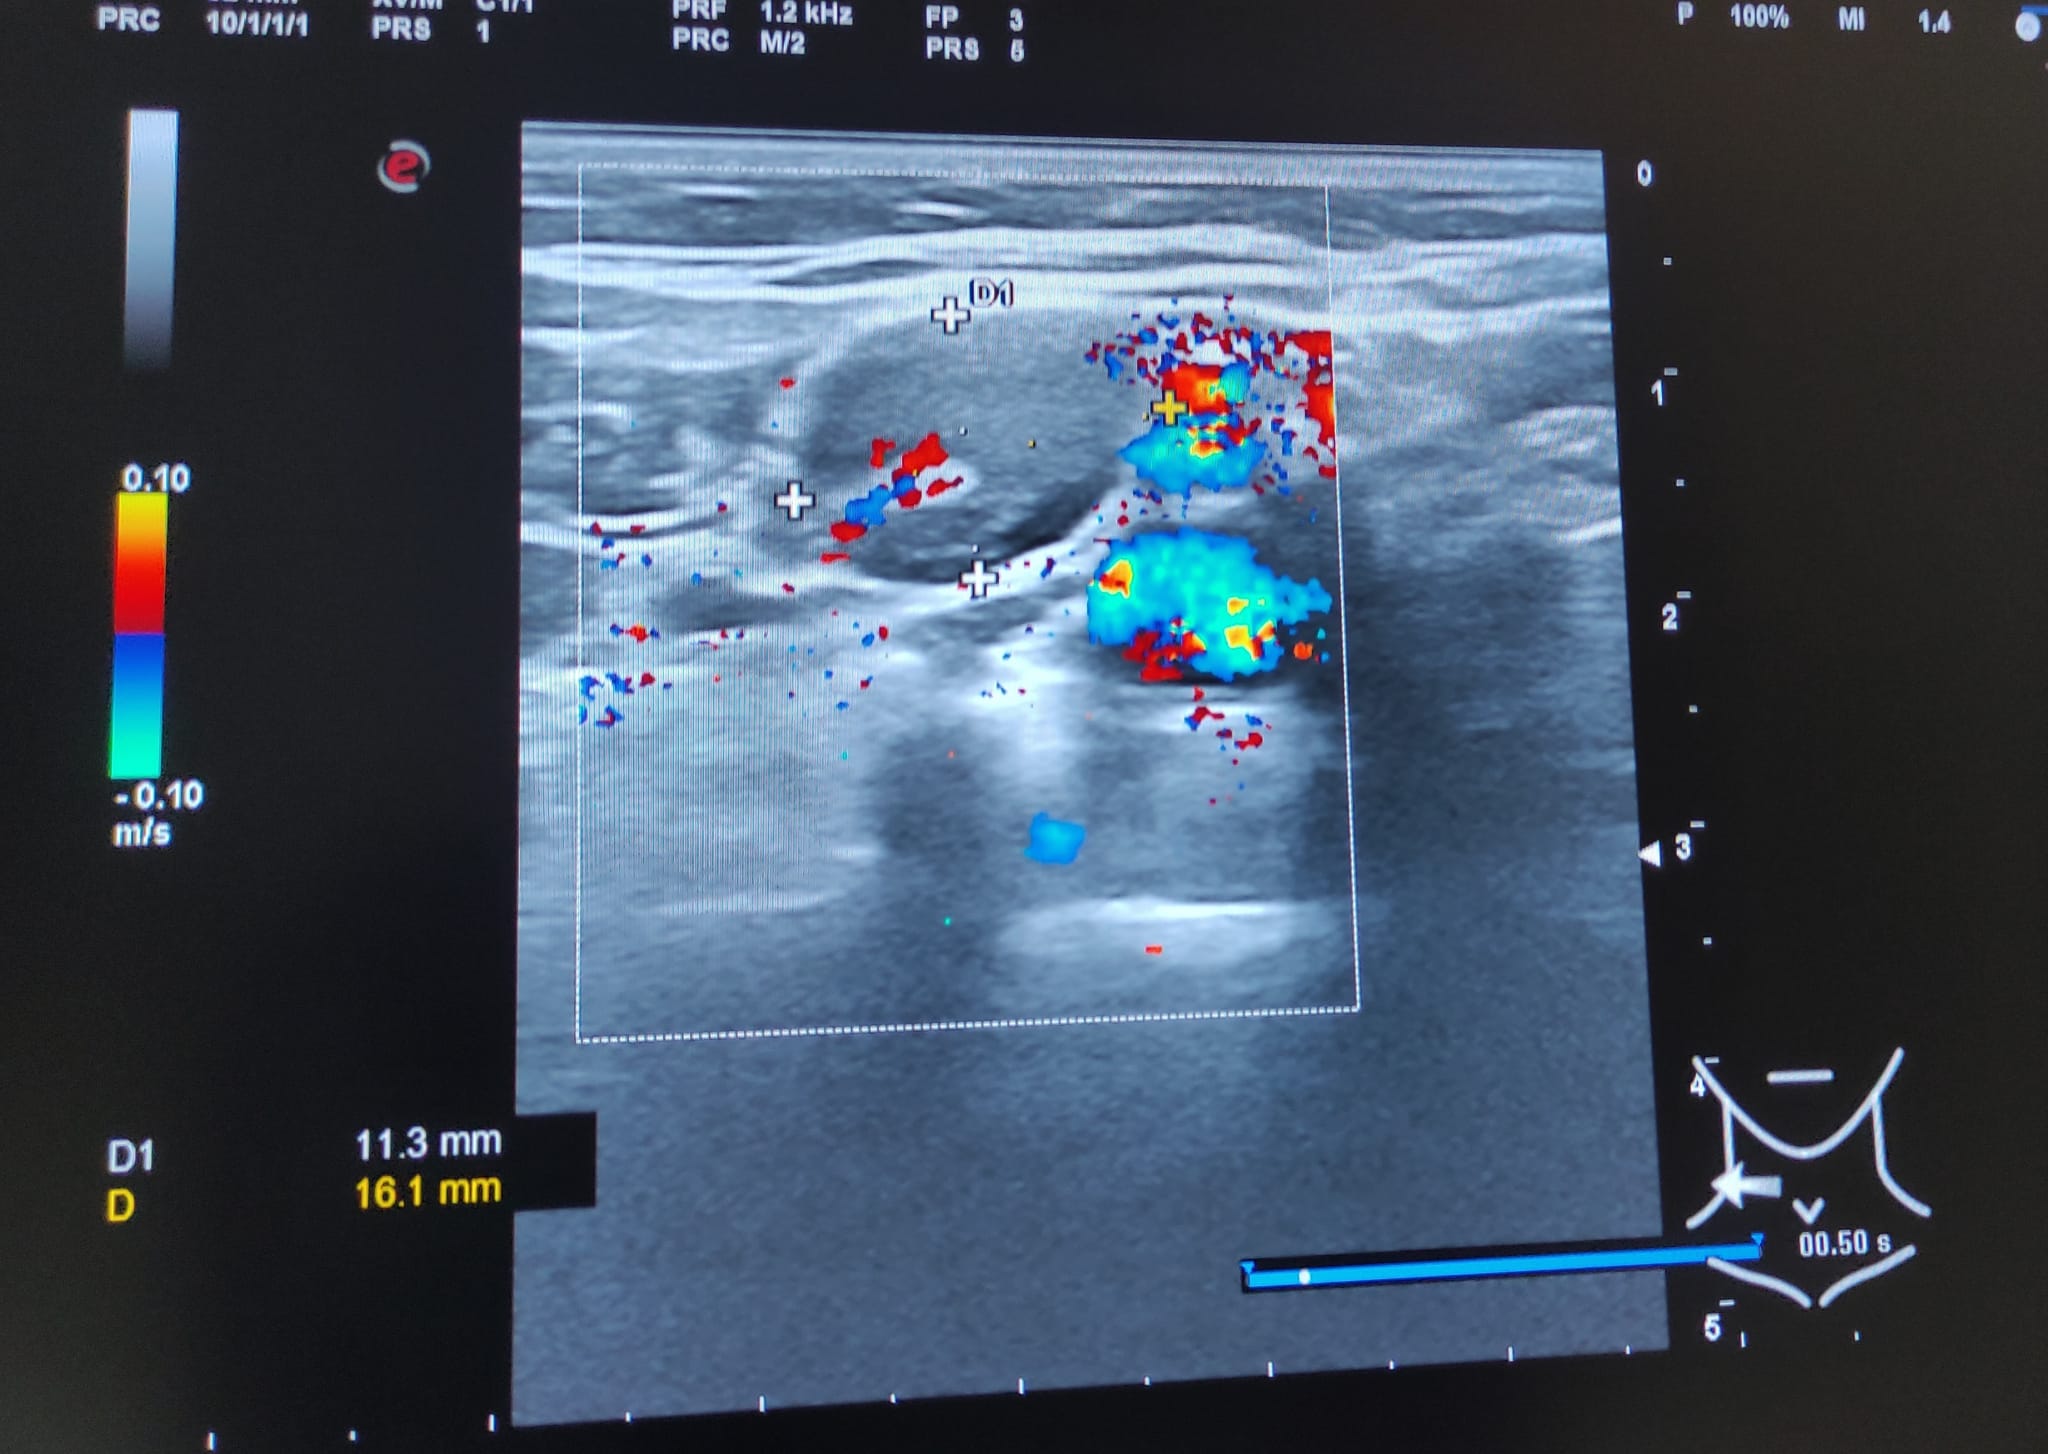

Hallazgos ecográficos

Múltiples adenopatías (más de 12) de varios tamaños siendo la mayor de 2 cm y de morfología redondeada, alguna sin hilio ni centro graso.

A los 3 meses se realiza nueva ecografía sin observar cambios significativos en las adenopatías ya visualizadas. Paciente permanece asintomática.